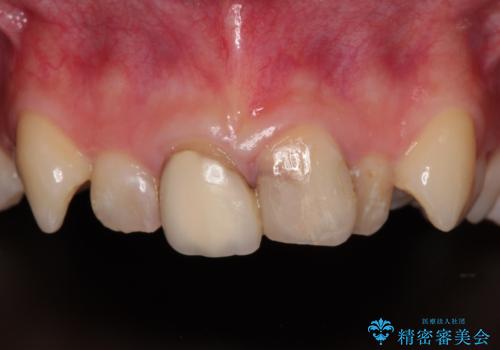

[ セラミック治療 ] 前歯の変色をきれいにしたい

担当医 大元洋佑

![[ セラミック治療 ] 前歯の変色をきれいにしたいの症例 治療前](https://seimitsushinbi.jp/wp/wp-content/uploads/2023/12/8095b301c8ea19cbf7179d372450bebf-500x350.jpg?v=1703129532)

![[ セラミック治療 ] 前歯の変色をきれいにしたいの症例 治療後](https://seimitsushinbi.jp/wp/wp-content/uploads/2023/12/528aed1286d6fd20e773cd5dfb0c7971-500x350.jpg?v=1703129602)